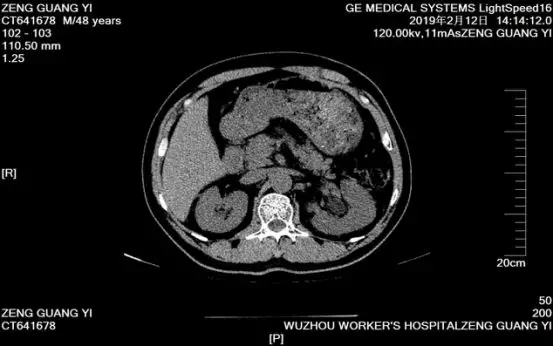

入院后,科室认真研判病情,认为左肾结石大而复杂,患者有腹部手术史,体外震波碎石病史,应用左侧输尿管软镜钬激光碎石不单创伤极小甚至无出血,而且可以一次性解除患者困扰已久的结石病患。手术历时约40分钟,顺利粉碎患者体内结石并取出体外,术后第二日患者便康复出院。出院前,医生还按照结石成分分析结果为他今后防治结石复发提供建议。

(图为曾先生术后复查CT片,横截面已无结石残留。)